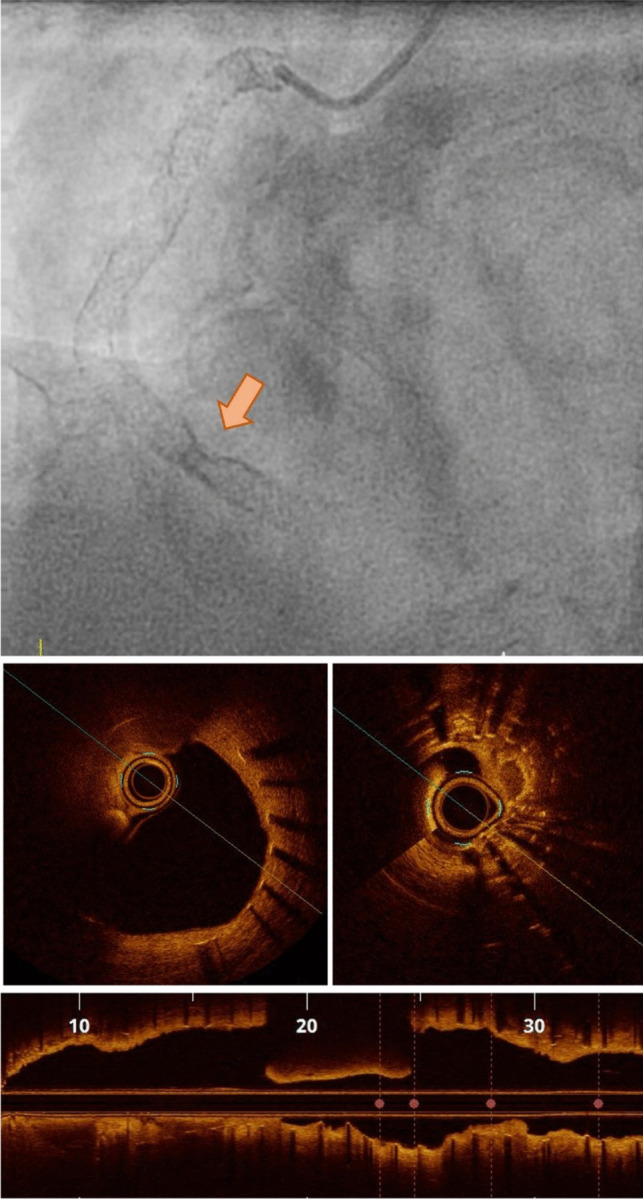

Recent findings: Despite the widespread use of DES and numerous improvements, recent clinical data indicate that ISR still occurs in 5-10% of PCI procedures, posing a considerable public health issue. The incidence, morphology, and clinical implications of ISR are determined by a complex interplay of several factors: the patient, stent, procedure, and vessel and lesion-related factors. Advancements in intracoronary imaging have provided greater insight into its patterns and underlying causes. Over time, treatment strategies have evolved, and current guidelines recommend an individualized approach using intracoronary imaging to characterize ISR's underlying substrate.